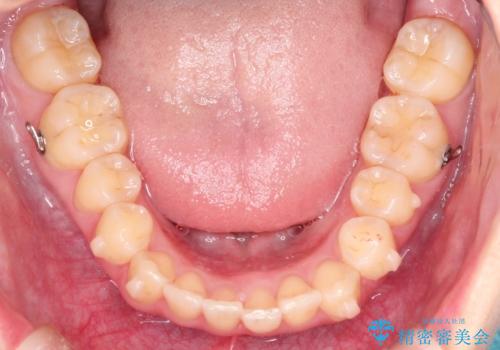

出ている前歯をインビザラインにて引っ込める

インビザラインにて上顎の歯を全体的に後方に移動させて前歯を引っ込める計画としました。

使用時間を守っていただけたので、比較的スムーズに矯正を終了することができました。